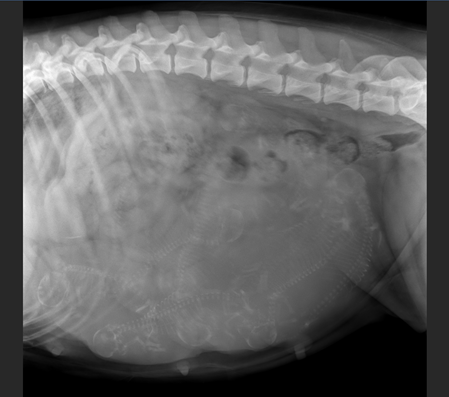

"Sind das Berner oder Frösche???"

unsere kleinste Hundemama erfreute sich am positiven Ultraschallbild

Wie viele werden es???